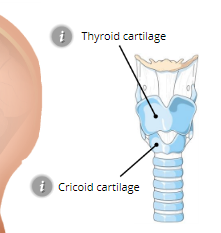

Thyroid Cartilage

Adams apple

Cricoid Cartilage

expands to allow large amounts of food to be swallowed